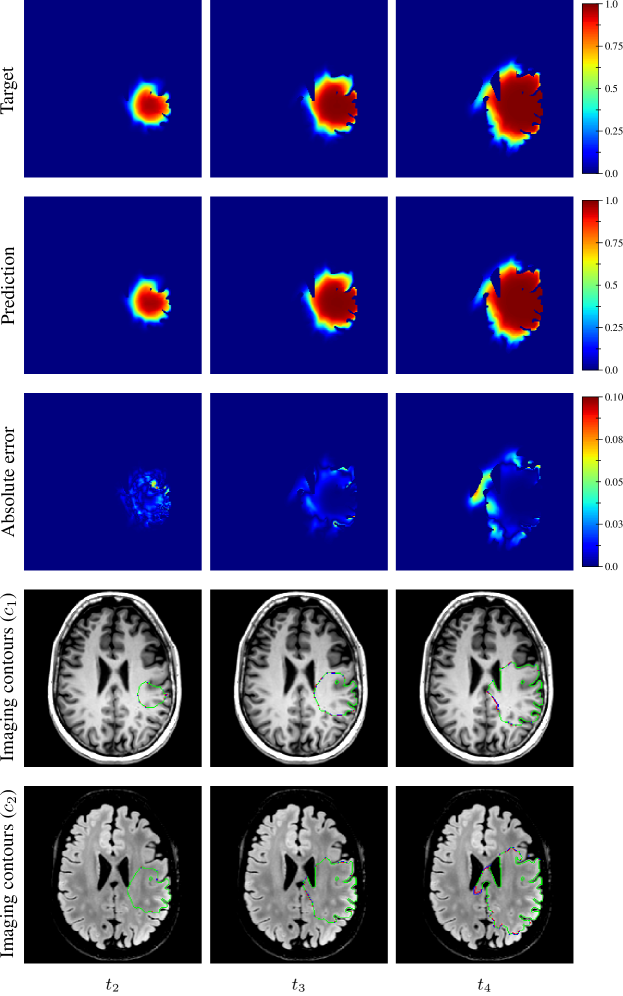

The distribution of the mean absolute error computed over the test set between the true and estimated tumour cell distributions at time t2subscript𝑡2t_{2} within the c>0.01𝑐0.01c>0.01 contour is summarised by a boxplot in Figure 7 (1st plot). The corresponding median value was 9.58×1039.58E-39.58\text{\times}{10}^{-3}. Boxplots of the Hausdorff distance and ASSD distributions computed over the test set between the true and estimated imaging contours at time t2subscript𝑡2t_{2} for threshold values c1=0.80subscript𝑐10.80c_{1}=0.80 and c2=0.16subscript𝑐20.16c_{2}=0.16 are provided in Figure 8 (1st plots). An example of true and estimated tumour cell density distributions at time t2subscript𝑡2t_{2} from the test set is depicted in Figure 9 (1st column), along with the corresponding absolute error map as well as the true and estimated imaging contours for threshold values c1=0.80subscript𝑐10.80c_{1}=0.80 and c2=0.16subscript𝑐20.16c_{2}=0.16. Additional examples are provided in Appendix C. All predicted tumour cell distributions at time t2subscript𝑡2t_{2} used in Figures 9, 7 and 8 were provided by the first network (Figure 5).

As for imaging time t2subscript𝑡2t_{2}, the distributions of the mean absolute error computed over the test set between the true and estimated tumour cell distributions at times t3subscript𝑡3t_{3} and t4subscript𝑡4t_{4} within the c>0.01𝑐0.01c>0.01 contour are summarised by boxplots in Figure 7 (2nd and 3rd plot, respectively). The corresponding median values were 1.38×1021.38E-21.38\text{\times}{10}^{-2} and 2.20×1022.20E-22.20\text{\times}{10}^{-2} for t3subscript𝑡3t_{3} and t4subscript𝑡4t_{4}, respectively. Boxplots of the Hausdorff distance and ASSD distributions computed over the test set between the true and estimated imaging contours at times t3subscript𝑡3t_{3} and t4subscript𝑡4t_{4} for threshold values c1=0.80subscript𝑐10.80c_{1}=0.80 and c2=0.16subscript𝑐20.16c_{2}=0.16 are also provided in Figure 8 (2nd and 3rd plots). The true and estimated tumour cell density distributions at times t3subscript𝑡3t_{3} and t4subscript𝑡4t_{4} are depicted in Figure 9 (2nd and 3rd column, respectively) for the same test case as for time t2subscript𝑡2t_{2}, along with the corresponding absolute error maps as well as the true and estimated imaging contours for threshold values c1=0.80subscript𝑐10.80c_{1}=0.80 and c2=0.16subscript𝑐20.16c_{2}=0.16. Additional examples are provided in Appendix C. A loss of accuracy in the estimated tumour cell density distributions over simulated time is observed in Figures 7, 8 and 9. The estimated tumour cell density distributions at times t3subscript𝑡3t_{3} and t4subscript𝑡4t_{4} used in Figures 9, 7 and 8 were computed using the reaction-diffusion model as described in Section 2.6 from (i) the cell density distribution predicted at time t2subscript𝑡2t_{2} provided the first network (Figure 5) and (ii) the predicted model parameters values provided by the second network (Figure 6).

Figure 9: Example of true (1st row) and estimated (2nd row) tumour cell density distributions at times t24subscript𝑡24t_{2-4} (1st to 3rd column, axial slices) along with the corresponding absolute error maps (3rd row) for a test tumour (d=43.47 mm2 yr1𝑑times43.47timesmillimeter2year1d=$43.47\text{\,}{\mathrm{mm}}^{2}\text{\,}{\mathrm{yr}}^{-1}$, ρ=11.22 yr1𝜌times11.22year1\rho=$11.22\text{\,}{\mathrm{yr}}^{-1}$, t1=94 dsubscript𝑡1times94dayt_{1}=$94\text{\,}\mathrm{d}$, t2=264 dsubscript𝑡2times264dayt_{2}=$264\text{\,}\mathrm{d}$). The imaging contours for threshold values c1=0.80subscript𝑐10.80c_{1}=0.80 and c2=0.16subscript𝑐20.16c_{2}=0.16 superimposed to the T1 and T2 FLAIR image are depicted in the 4th and 5th rows, respectively. The blue, red, and green segments respectively correspond to the target, prediction, and overlapping contour voxels. The predicted cell distribution at time t2subscript𝑡2t_{2} was provided by the first network (Figure 5). The estimated cell distribution at times t3subscript𝑡3t_{3} and t4subscript𝑡4t_{4} were computed using the reaction-diffusion model from the cell distribution predicted at time t2subscript𝑡2t_{2} and the predicted model parameters values provided by the second network (Figure 6).